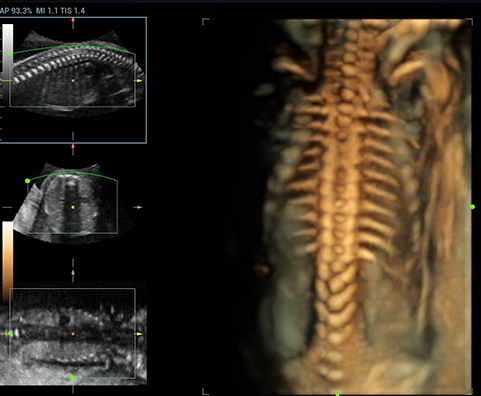

AdemÃĄs de una calidad superior de la imagen, el Resona 7 tambiÃĐn mejora las capacidades de investigaciÃģn clÃnica gracias al revolucionario V Flow para la evaluaciÃģn hemodinÃĄmica vascular y la adquisiciÃģn de planos mÃĄs inteligente a partir de un conjunto de datos 3D para el diagnÃģstico CNS fetal. Combinando el funcionamiento multitÃĄctil mÃĄs intuitivo basado en gestos y todas las funciones clÃnicas esenciales, el Resona 7 estÃĄ realmente encabezando nuevas ondas en la innovaciÃģn del campo del ultrasonido.